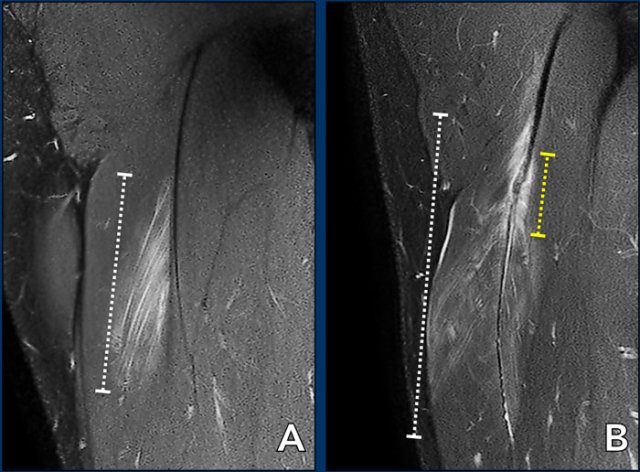

Total length of the edema is noted (white dotted line). Now take a closer look at the tendon (yellow dotted line) and continue reading.

Length of tendon distortion

When the tendon looks normal, straining is probable low grade.

Tendon thickening, tendon waviness, high signal of the tendon can all be signs of higher grade straining.

Case 1: normal tendon.

Case 2 slightly thickening and wavy aspect of a short length of the tendon.

Case 3: obvious thickening and waviness

All these signs have to be described in your report.

Total length of the distorted tendon is noted.

Both length of edema and distorted tendon are measured and noted in the report.

In this case, biceps femoris tendon injury was classified as grade 3 partial injury, since the length of the edema is > 15cm (white dotted line) and the length of the distorted tendon is > 5cm (yellow dotted line).

Two more cases to demonstrate this classification.

A muscle edema 5-10cm (white dotted line) present at the MTJ without architectural distortion of the tendon, classified as BAMIC 2b.

B muscle edema >15cm (white dotted line), at the MTJ / intramuscular tendon, tendon distortion > 5cm (yellow dotted line). The tendon shows disruption with loss of low signal intensity within the tendon along with a wavy appearance indicating focal loss of tension. BAMIC 3b/c.